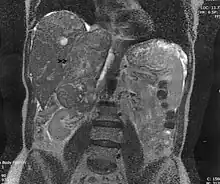

Leiomyosarcoma of the adrenal vein. Coronal view of abdominal MRI. Tumor (arrow) extends from the superior pole of the right kidney to the right atrium.